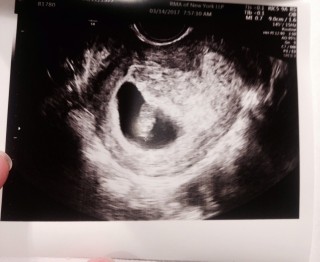

CRL:21.2ミリ

心拍数:181bpm

エコーでは細い手足とへその緒が見えました。9w0dの大きさとのこと。このまま元気に育ちますように…!